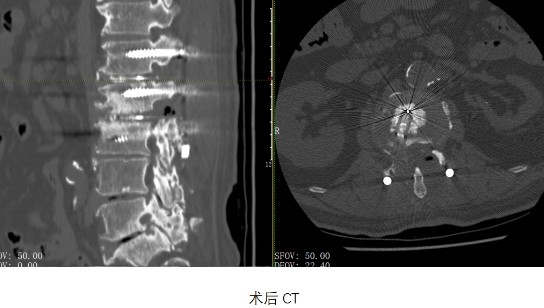

滬甬兩地脊柱團隊精準操作,經過3個半小時的高強度手術,手術團隊相繼完成腰1-2、2-3椎板切除椎管擴大減壓、椎間橫突間植骨融合、脊柱滑脫復位椎弓根釘內固定、脊髓和神經根粘連松解、腰椎翻修內固定取除術等多項手術,最終都獲得成功。

“這些螺釘至今堅固如初,拆除時我仿佛看見了當年前輩們手術的場景。雖然當年的術式在如今看來是不完整、存在缺陷的,但是考慮到當年的條件,患者能夠保持20年的療效,已然非常不錯!”朱曉東教授感嘆道。